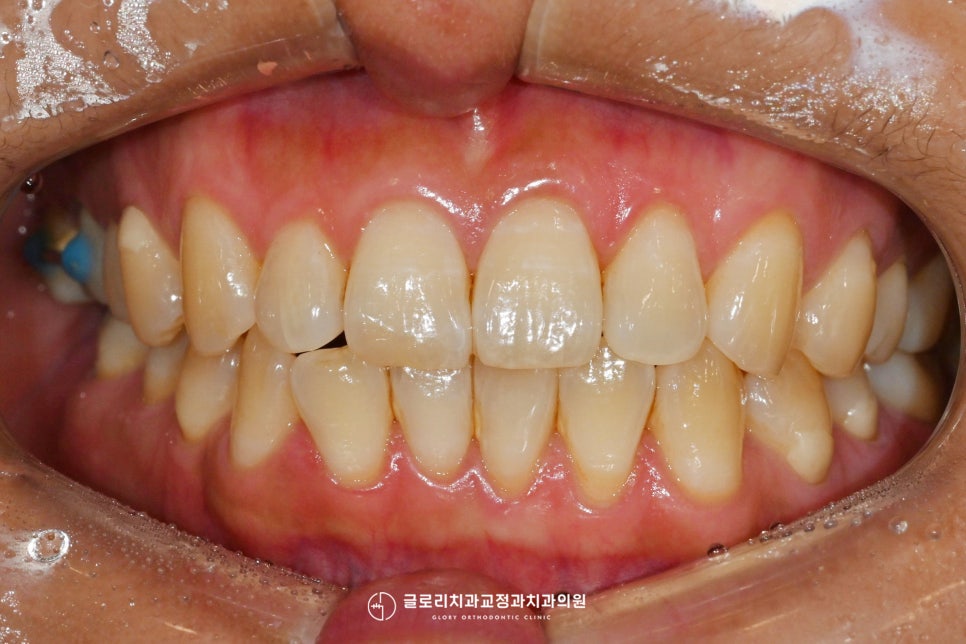

연결해둔 곳을 정확히 확인하기 위해

구강 내를 천천히 둘러보았습니다.

위치는 오른쪽 위 구치부로

아래쪽과 대합이 되는 곳에

철사로 연결을 해두었는데요.

이렇게 철사로 두 개 구치부를 연결해둔 이유는

치아 정출 때문이었습니다.